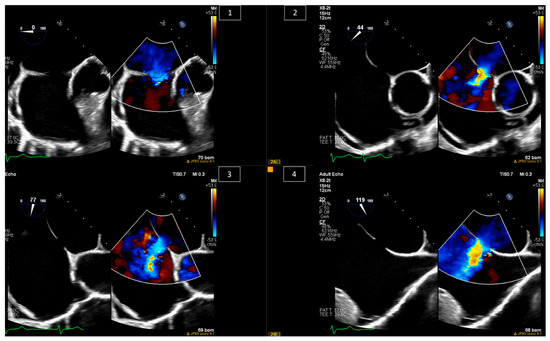

6. Baffle Complications in Atrial Switch Operations